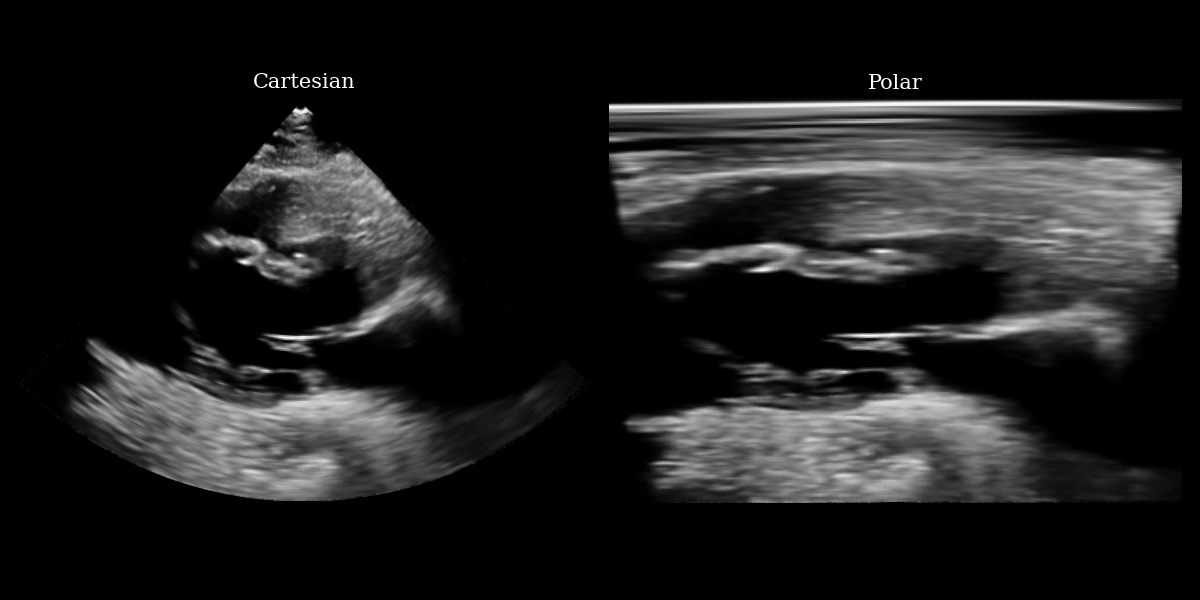

# NOTE: this is a synthetic PLAX view image generated by a diffusion model.

url = "https://raw.githubusercontent.com/tue-bmd/zea/main/docs/source/notebooks/assets/plax.png"

response = requests.get(url)

img = Image.open(BytesIO(response.content)).convert("RGBA")

# Split channels

r, g, b, a = img.split()

# Composite onto a black background (RGB = 0,0,0)

black_bg = Image.new("RGBA", img.size, (0, 0, 0, 255))

img = Image.alpha_composite(black_bg, img)

img = img.convert("L")

img_np = np.asarray(img).astype(np.float32)

img_tensor = ops.convert_to_tensor(img_np)

img_polar = inverse_scan_convert_2d(img_tensor, image_range=(0, 255))

img_polar_np = ops.convert_to_numpy(img_polar)

# plotting

fig, (ax1, ax2) = plt.subplots(1, 2, figsize=(12, 6))

ax1.imshow(img_np, cmap="gray")

ax1.set_title("Cartesian", fontsize=15)

ax1.axis("off")

ax2.imshow(img_polar_np, cmap="gray")

ax2.set_title("Polar", fontsize=15)

ax2.axis("off")

plt.tight_layout()

plt.savefig("cartesian_polar.png")

plt.close()

Cartesian Polar input